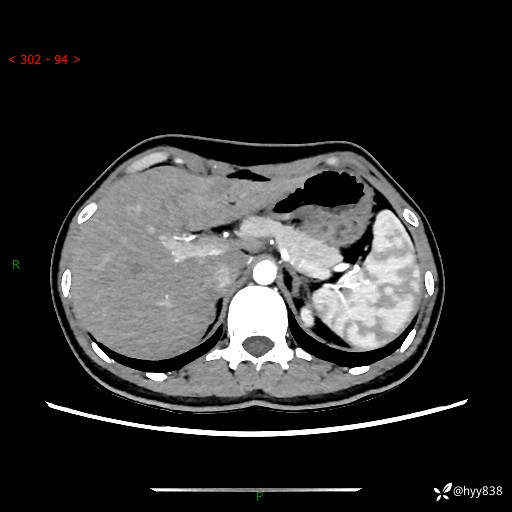

性别:女

年龄:23岁

简要病史:外院发现肝结节,来我院进一步增强确诊

上腹部CT平扫+增强